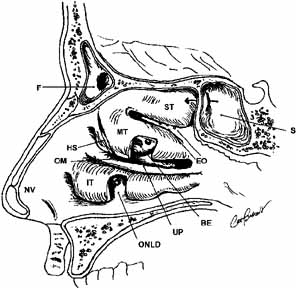

malignant and are discussed in detail elsewhere. The tears drain through the superior and inferior puncta and canaliculi

and are pumped into the nasolacrimal sac by the orbicularis muscle sphincter

action. The nasolacrimal sac lies in a fossa between the anterior

lacrimal crest of the maxillary bone and the posterior lacrimal crest

of the lacrimal bone, and is wrapped by the thick anterior and thinner

posterior limbs of the medial canthal tendon. The puncta are 2 mm

in height, the canaliculi are 8 mm in length, and the sac is 12 to 14 mm

in height, with its fundus extending slightly above the medial canthal

tendon. The nasolacrimal duct then travels inferolaterally and slightly

posteriorly in its bony course to the inferior turbinate. The valve

of Rosenmuller is located at the junction of the common canaliculus

and sac, the valve of Krause between the sac and duct, and the valve

of Hasner at the ostium to the inferior meatus. The entry in an external

dacryocystorhinostomy is at the anterior middle meatus. Extraocular Muscles Except for the inferior oblique, the extraocular muscles all arise from